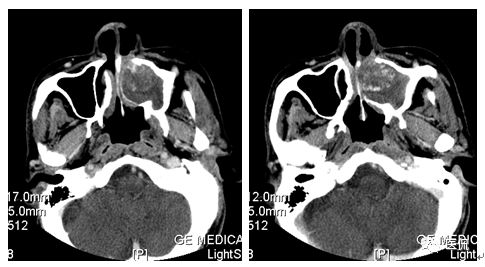

增强水平位FST1WI

CT平扫及增强示:左侧上颌窦及鼻腔可见软组织密度影,呈膨胀性生长,周围骨质压迫性吸收破坏,累及左眶,病灶密度不均匀,周边区可见点状钙化,增动脉期轻度强化,局部见小灶性稍高密度区,静脉期病灶内见不均匀明显强化,CT值最高达117HU,延迟期强化范围有所增大。

影像学表现呈软组织密度,多不均匀,表现为高低混杂密度,病变窦腔内息肉、血肿、坏死、感染共存,是病灶密度不均匀的主要原因,息肉反复出血、血管机化亦为其成因之一。病灶内钙化,可为团块状或小片状,可能为病变组织坏死后钙质沉着所致。因为病变组织内有大量炎性细胞浸润和丰富的毛细血管,增强后常有强化。有文献报道病灶增强中心区强化不明显,外周呈轻度强化,推测病灶内虽然血管丰富,但中心区容易出现血流动力学障碍,血管内常有血栓形成,中心区易发生出血坏死,另外,可能与增强扫描延迟时间选择不当有关。

本例病灶较大,周围骨质可见吸收破坏,并累及眼眶,病灶内少量钙化,增强扫描具有一定特征性,表现为动脉期轻度强化,局部见小灶性稍高密度区,静脉期病灶局部呈明显强化,CT值最高达117HU,延迟期强化范围有所增大,呈延迟渐进性强化的特点,推测为病灶内出血所致。